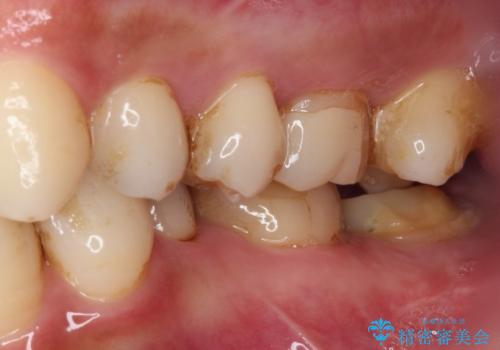

- かかりつけ医にて、歯の高さが不足しているためセラミッククラウンの装着はできないと言われたとのことで来院された患者様です。

診察したところ、確かに歯の高さは不足していましたが、土台の立て直しや歯の削り方を調整することでオールセラミッククラウンでも補綴可能と思われました。

ただし、クラウンの厚みは極力薄くした方が維持力が増すため、高強度のフルジルコニアクラウンにて補綴治療することとしました。

仮歯が途中外れることもなく、無事に補綴治療を行うことができました。

歯石や磨き残しなどが多いため、今後クリーニングを行っていきます。